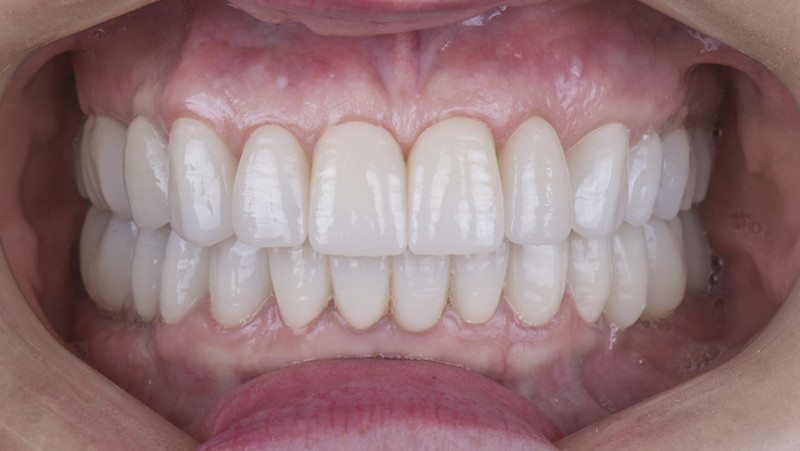

Установка коронки на зуб

Провели швейцарскую профгигиену. Перелечили зубы с несостоятельными пломбами и воспалениями. Удалили 7 зубов на верхней и нижней челюсти с одномоментной имплантацией 9 имплантатами, костной пластикой и пластикой десны. После приживления имплантатов установили временные коронки. Изготовили и установили абатменты Procera и 28 единиц керамических коронок EMAX.